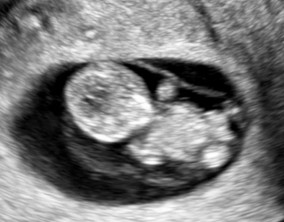

남성 요인·다낭성에도 1차 성공

이유정 원장님을 믿고 따르며 인내하다 보니 결국 좋은 결과를 얻을 수 있었습니다. 단순한 치료가 아니라 환자의 상황을 깊이 이해하고 맞춤형으로 이끌어주신 점이 큰 힘이 되었…